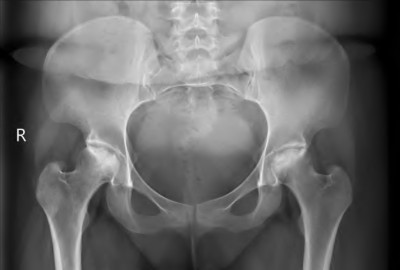

A 75-year-old man underwent total hip arthroplasty 10 years ago. He now reports mild groin pain which has been increasing lately. What is the most likely explanation for the finding in Figure A indicated with the arrows?

Osteolysis of the pelvis is a common complication associated with total hip arthroplasty. Osteolysis affects sockets with and without cement, and has been attributed to the biologic reaction to wear debris. With well-fixed cementless sockets, an expansile pattern of osteolysis is usually seen.

The radiographic appearance has a radiolucent area that starts at the implant-bone interface and expands into the cancellous bone away from the implant.

This pattern of osteolysis can be explained with the concept of effective joint space. This concept states that joint fluid and wear particles will flow according to pressure gradients and follow the path of least resistance.

The Level 5 review article by Chiang discusses osteolysis in further depth.